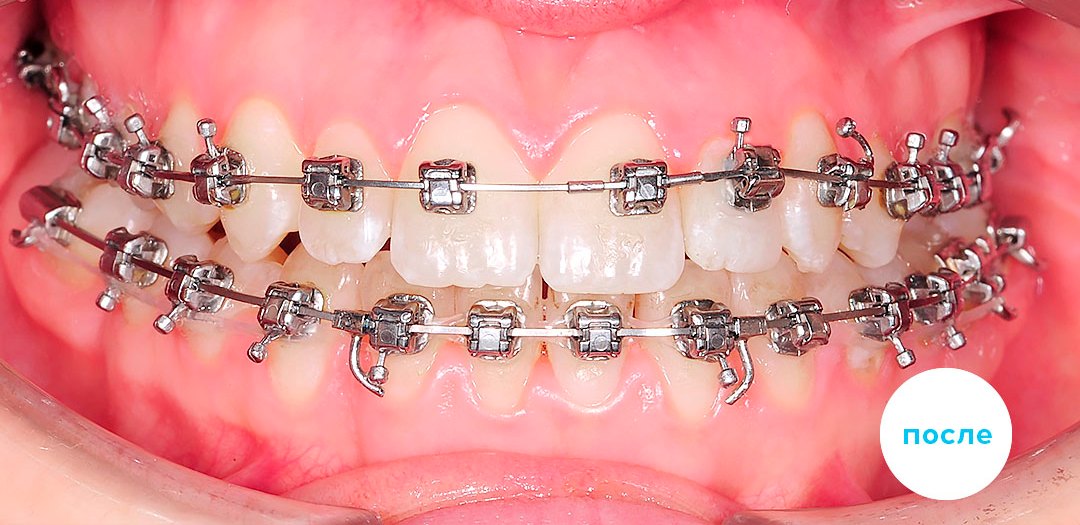

После

После

После